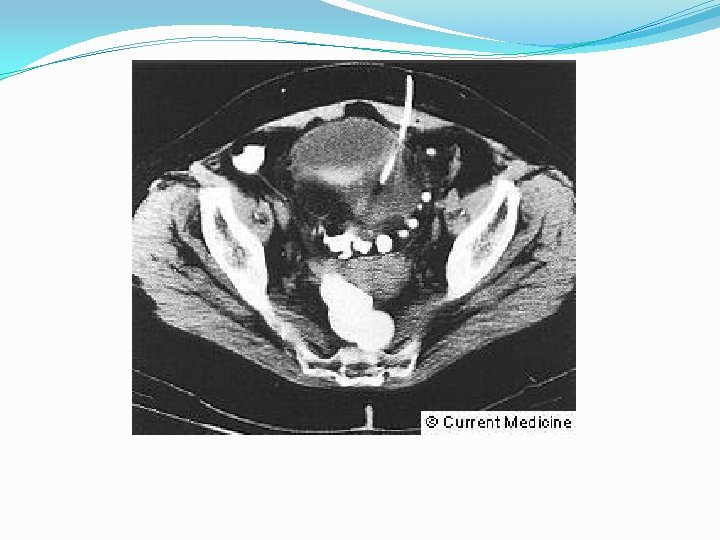

• Rx Simple • Tórax: • Abdomen • Enema baritado y colonoscopia: contraindicados en fase aguda • Enema hidrosoluble • TAC helicoidal • Engrosamiento pared Intestinal • Grasa mesentérica en franjas • Abscesos • ECO • Engrosamiento pared colónica • Masas

• Rx Simple • Tórax: Perforación • Abdomen • Dilatación de ID y de IG • Obstrucción intestinal • Opacidades de partes blandas: abscesos • Enema baritado y colonoscopia: contraindicados en fase aguda • Enema hidrosoluble • TAC helicoidal • Engrosamiento pared Intestinal • Grasa mesentérica en franjas • Abscesos • ECO • Engrosamiento pared colónica • Masas

Diagnóstico – TAC – Cistoscopia – Cistografía – Colonoscopia – Enema baritado